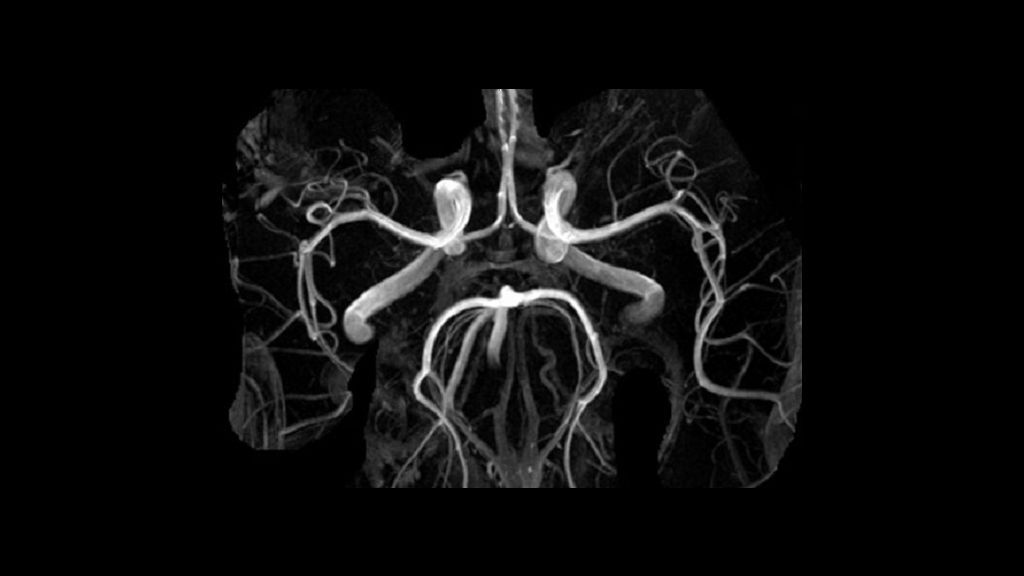

- На серии снимков четко визуализируется брюшная часть аорты на всем ее протяжении. Оценивается форма сосуда, толщина его стенок. Легко определяются отложения холестерина (холестериновые бляшки), кальцинаты – признаки атеросклероза. Четко визуализируются и другие патологии сосудистой стенки – аневризмы, расслоение, аномалии развития. Оценивается кровоток, проходимость сосуда.

- По мере накопления контраста на снимках визуализируются другие артерии брюшной полости – чревный ствол, желудочные, печеночные, почечные, селезеночные артерии, артерии брыжейки.